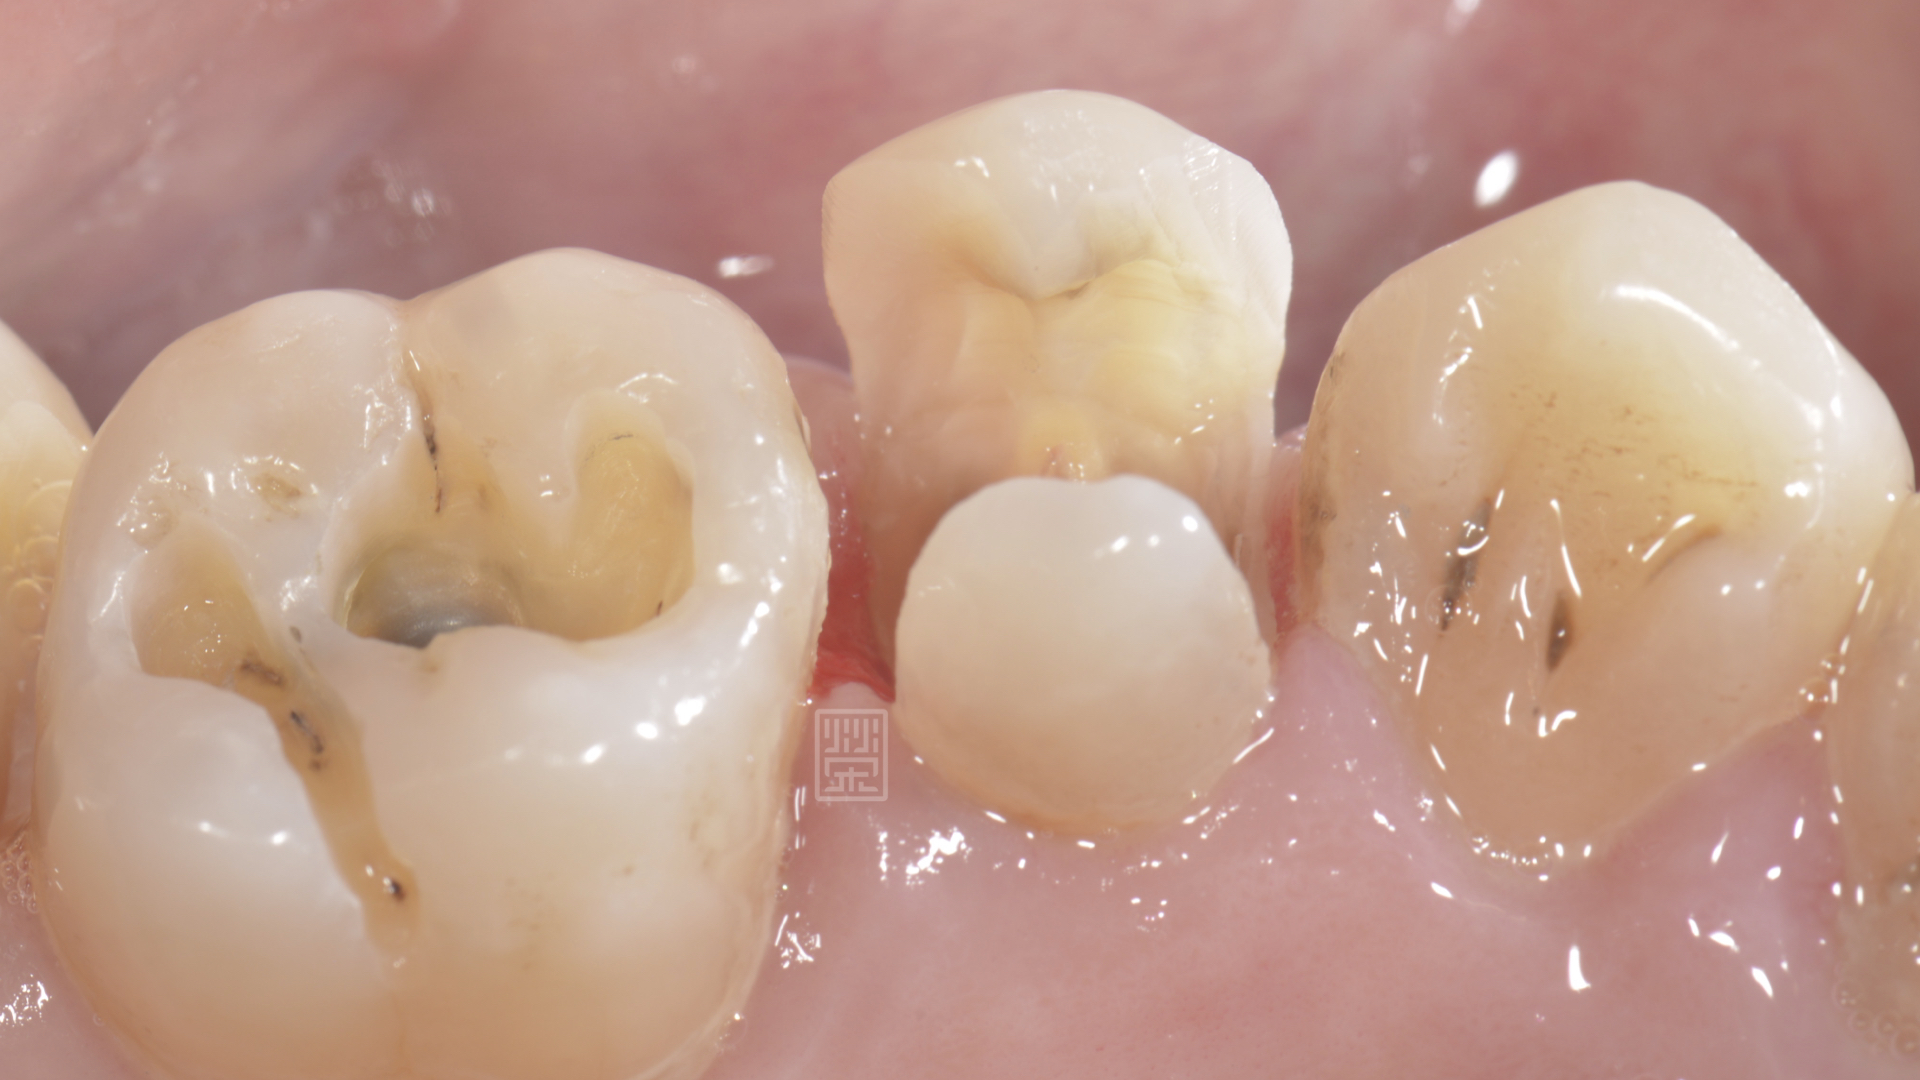

利用黏著式嵌體對牙齒只需做最少的修磨,但是在頰側,為了有好的外觀,所以包覆到牙齦邊緣,空間厚度以最小厚度0.3毫米為製作空間,減少對牙齒的傷害,完成全瓷嵌體後,恢復理想的功能與美觀,也利用全瓷嵌體的特性,保存了牙齒,減少牙齒需要拔牙的可能性。

全瓷嵌體修復治療完成